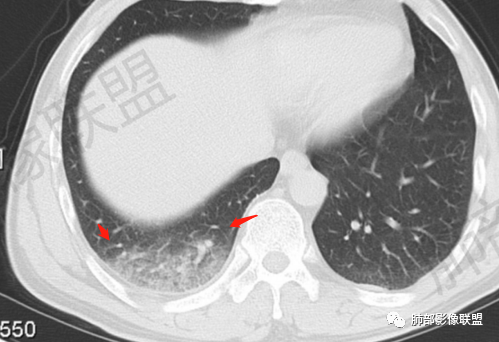

一切∮随缘:右肺肺尖段多发结节片状高密度影,部分伴有反晕征,边界欠清楚,部分伴有纤维索条,支气管显示欠佳,小叶间隔增厚,周围血管束增粗,(考虑结核可能)右肺下叶胸膜下片状磨玻璃影,与胸膜相贴,与肺组织交界面清楚,实性偏少,考虑:肺栓塞?病毒?OP?

王秀仙:右肺上叶可见结节及斑片影,部分呈反晕征,边缘清晰,右肺下叶后基底段胸膜下磨玻璃样实变影,呈扇形,内部见细网格,右肺上叶考虑结核。右肺下叶考虑肺栓塞,鉴别病毒肺炎。

小兜:男,47岁,胸闷气短入院,一天前无明显诱因胸闷气短伴呼吸困难,夜间出现右侧胸痛,与呼吸及体位有关,曾有一次痰中带血。CT示右肺上叶尖段多发结节,条索影,可见树芽征及反晕征。右肺下叶胸膜下片状密度增高影,宽基底与胸膜相连,成扇形。综合考虑右肺上叶尖段结核可能;右肺下叶肺栓塞?病毒性肺炎?

琦遇:右肺上叶结核基本明确,考虑活动性,有钙化、反晕征、结节、斑片、纤维索条;右肺下胸膜下GGO,内大小网格,胸膜增厚,患者胸痛,咯血,首先考虑PE,下一步增强CTPA以明确

微微笑:右肺上叶斑片、结节、索条影,边缘较清晰,见反晕斑片,考虑结核。右肺下叶宽基底磨玻璃影,网格样改变,胸膜增厚,结合病史,考虑栓塞。

右上叶,多灶性、多态性,烟花征,结核应该没问题

后基底段,胸膜下,这个没问题吧

我们看看病变的形态、密度、边缘、内部改变

GGO密度

边缘不清

可惜没有重建,楔形?

细网格明显

支气管通畅,壁增厚

血管增粗